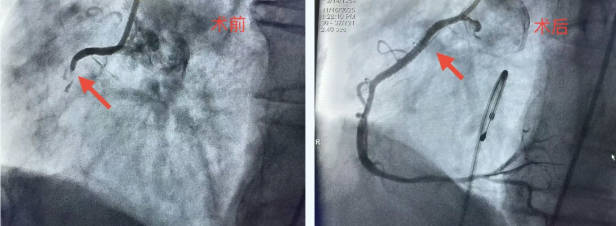

术中,医疗团队为患者施行了冠状动脉造影、球囊扩张、支架植入及血管内超声检查。造影结果显示患者冠脉存在严重狭窄。在手术关键阶段,患者突发心室颤动,情况危急。团队立即实施电除颤及心肺复苏,患者心律迅速恢复,手术得以继续。最终,手术团队成功植入支架,血管血流恢复良好。